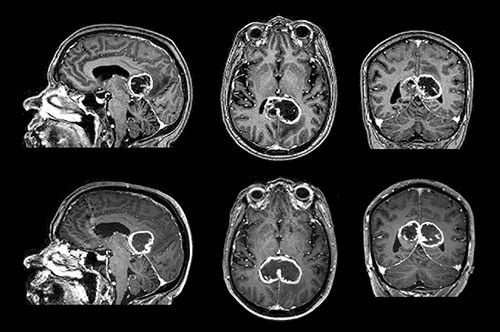

Nederste del av figuren viser den samme svulsten etter 16 dager, der den har vokst fra 27,4 cm³ til 37,6 cm³, en vekst på 37  %. Dette tilsvarer en doblingstid på 32 dager, forutsatt eksponentiell vekst. I litteraturen er det få systematiske undersøkelser av veksthastighet og doblingstid av glioblastomer in vivo. De få studiene som finnes angir doblingstider på 10 – 95 dager.